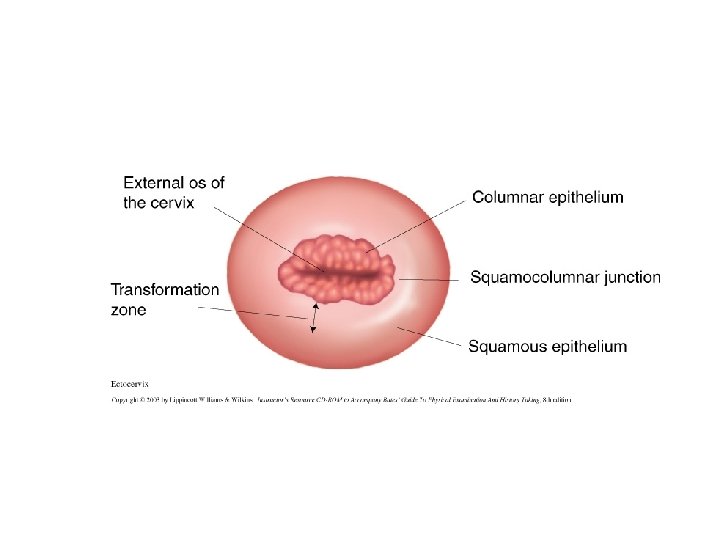

Squamocolumnar Junction